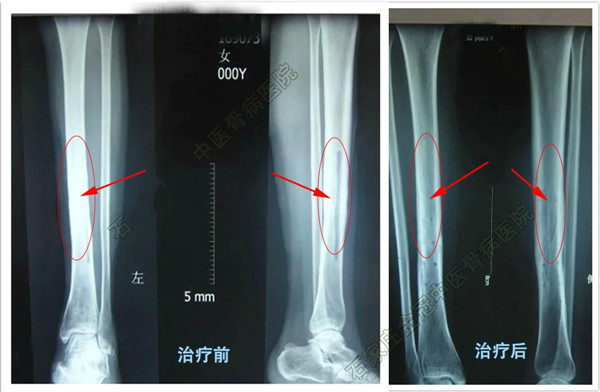

骨髓炎治疗前后对比CT图